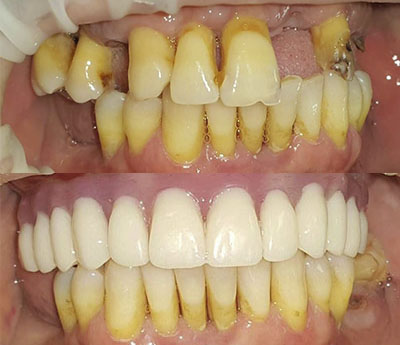

Sistemul Fast&Fixed este o alternativă imediată. Această procedură îți va permite să-ți recapeți zâmbetul și încrederea în sine într-un timp scurt. Deși rezultatul este imediat, durata de viață a acestui implant este pentru o perioadă îndelungată.

Este un sistem inovativ care permite o fixare rapidă și de lungă durată a dinților lipsă. În acest caz se folosește osul nativ al pacientului. În acest fel sunt eliminate alte intervenții adăugătoare, cum ar fi creșterea masei osoase. Acest sistem presupune doar câțiva pași: consultarea, elaborarea unui set de analize, amprentarea dentară, inserarea implanturilor provizorii, refacerea arcadelor dentare, iar la final fixarea danturii definitive. De la consultare până la obținerea unui zâmbet impecabil te despart doar 24 de ore.